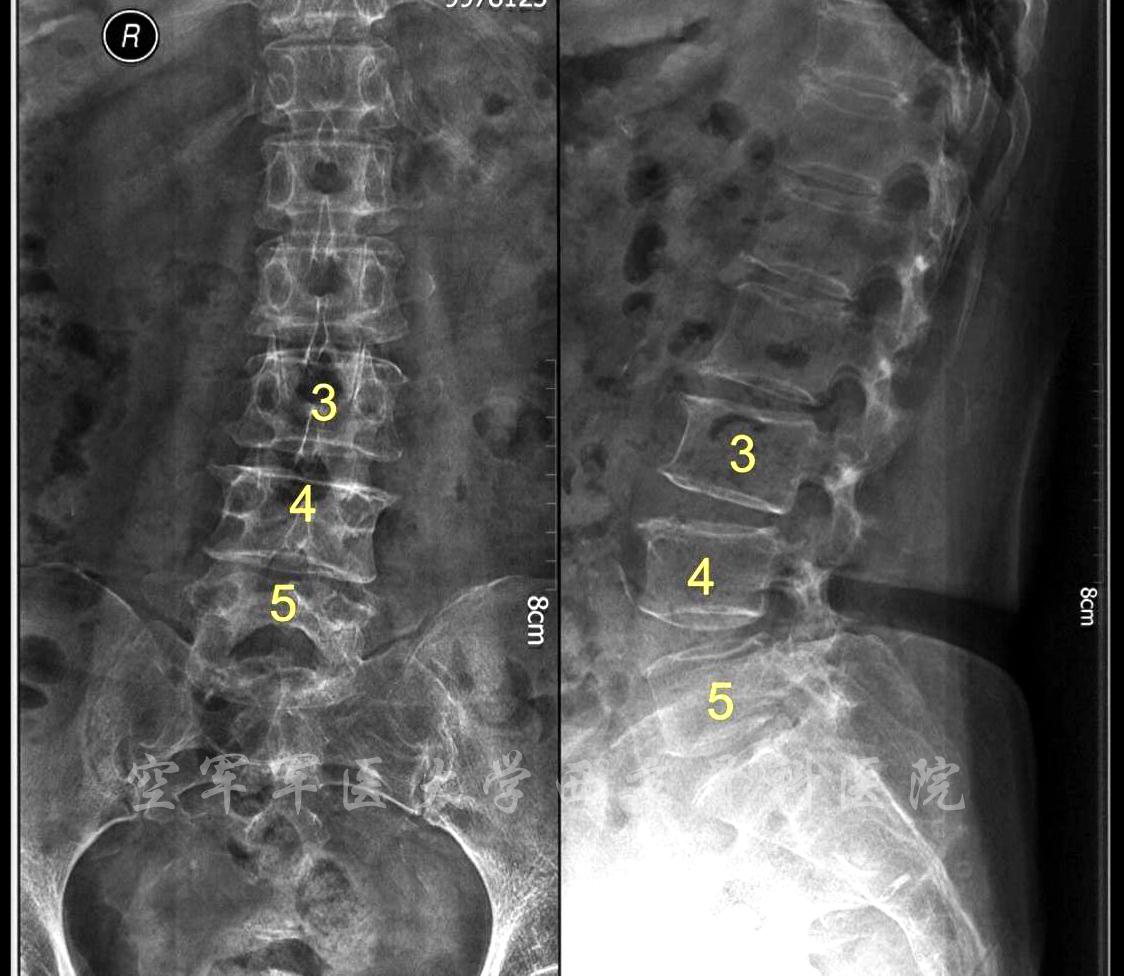

患者:男,74岁

主诉:腰背部疼痛3年,伴间歇性跛行半年。

查体:双侧直腿抬高试验-,双侧股神经牵拉试验-,双下肢皮肤感觉正常。双下肢肌肉无萎缩,肌力未见异常。双侧膝跳反射减弱,双侧跟腱反射消失。双侧病理征阴性。双侧髌阵挛、踝阵挛未引出

诊断:腰椎管狭窄症(L3-5)

术前X线正侧位片